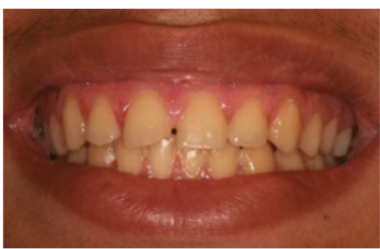

牙龈切除术是通过手术刀、电刀或者激光切除因牙周炎或药物影响而增生肥大的牙龈组织、后牙某些部位的假性牙周袋,以及一些妨碍进食、口腔卫生清洁的瘤样增生物。

通常情况下,医生会通过洁治、刮治等牙周基础治疗进行控制,若增生的牙龈仍然无法消退,才会通过牙龈切除术来治疗。

电刀怎么洗我以为只要洗个牙,医生你怎么还拿起了手术刀?_https://www.jmylbn.com_新闻资讯_第4张

治疗前

电刀和激光都有止血功能,因此这种手术出血量较小,愈合时间也不会过长,大家也不必过度抗拒。